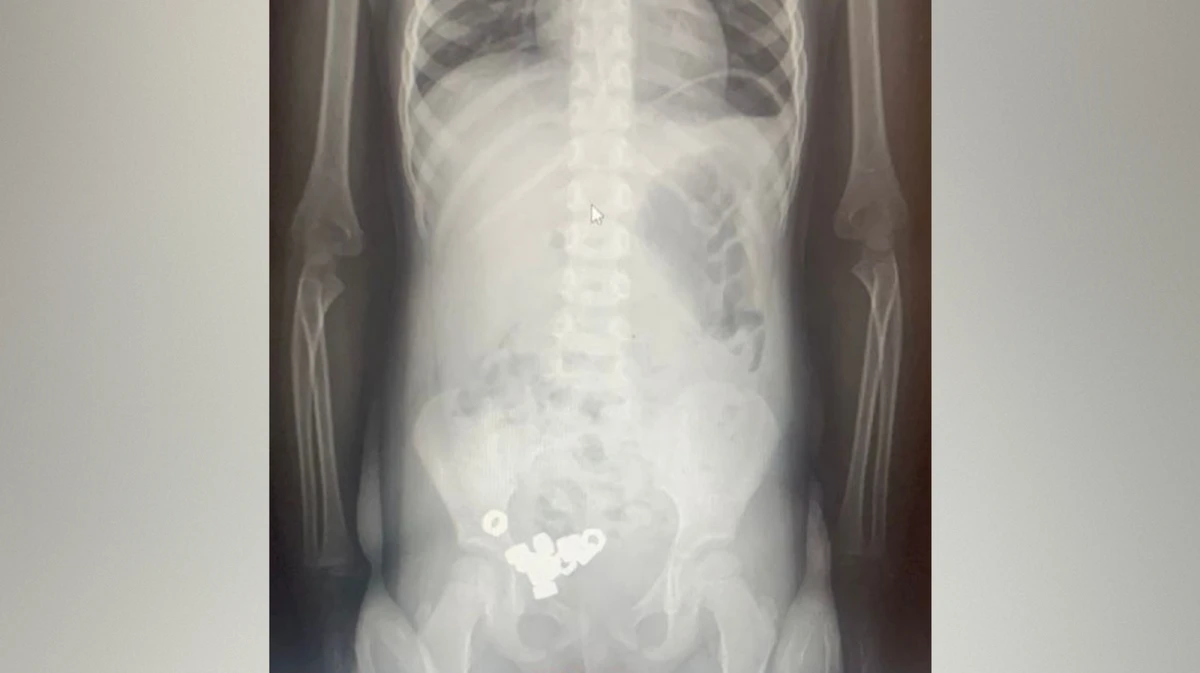

Ребенок съел вату

Ребенок съел вату 105 фото